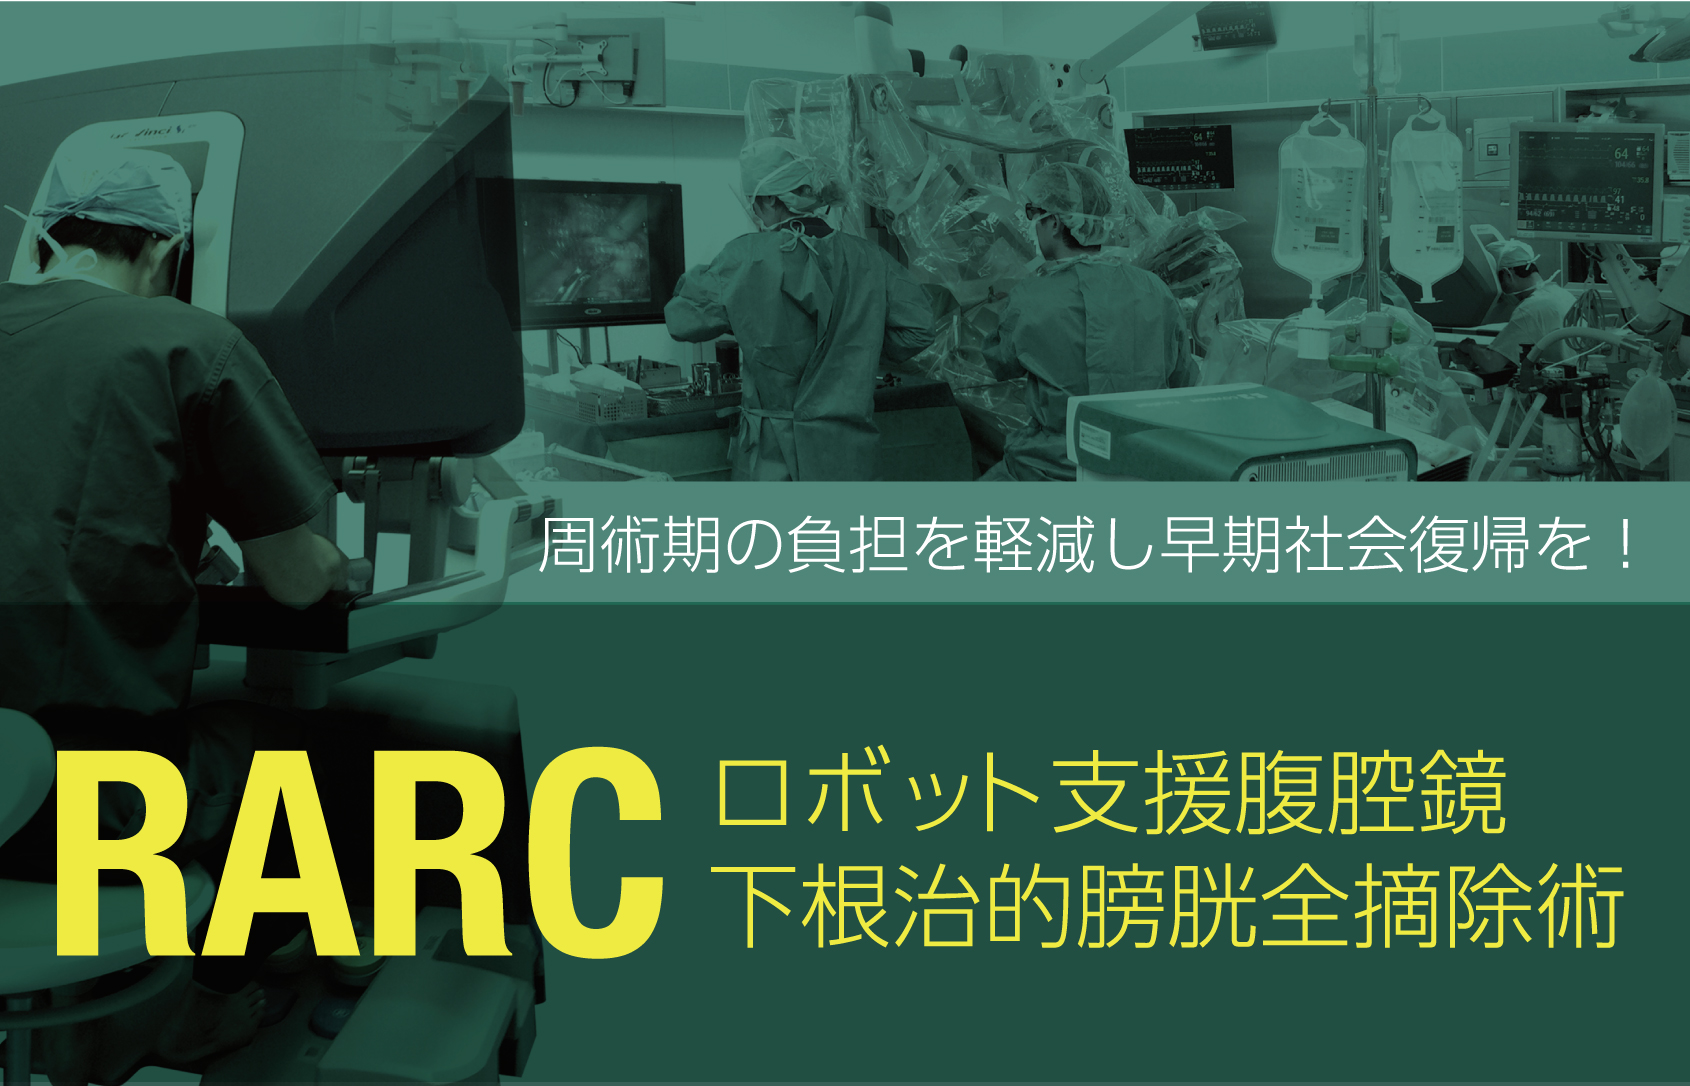

究める鏡視下膀胱全摘術・尿路変向術 Level up LRC, RARC | 三木。メジカルビュー社|泌尿器科|究める鏡視下膀胱全摘術・尿路変向。ロボット支援膀胱全摘除術(RARC) | 岩手医科大学 泌尿器科学講座。★3月精米★ 令和6年産 福井県産 いちほまれ 5kg 白米 精米。膀胱がん【泌尿器科疾患について】 - 東京慈恵会医科大学 泌尿器科。膀胱がん|KOMPAS。手術手技(膀胱全摘除術) | 領域情報 | アステラスメディカルネット。膀胱がん|KOMPAS。周術期の負担を軽減し早期社会復帰を!「ロボット支援腹腔鏡下。腎盂尿管移行部狭窄症に対するロボット支援腹腔鏡下腎盂形成術。朝倉書店『内科学』(第12版)デジタル付録。腹腔鏡下尿膜管摘出術及び左腎摘出術 - Olympus Professional。ロボット手術の定番!新品、未使用です。間違って2冊買ってしまったので、ページを開いてもいないため、本屋さんの「売上スリップ」も付いたままの全くの新品です。膀胱がんの外科治療について | 小野薬品 がん情報 一般向け。